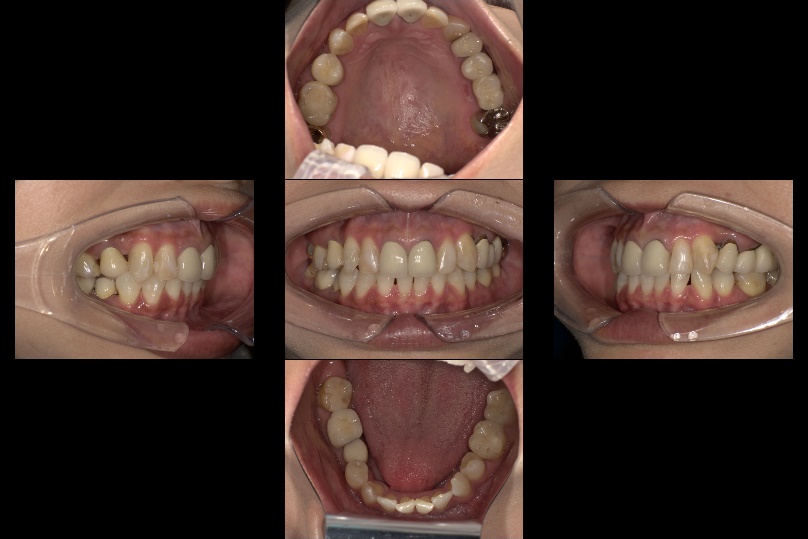

| 主訴 | 下の前歯のガタガタが気になる |

| 診断 | 受け口+叢生(ガタガタ) |

| 治療期間 | 1年8カ月 |

| 治療費用 | 矯正費用¥792,000(税込) +補綴費用924,000(税込) +ホワイトニング |

| 院長コメント | マウスピース矯正で受け口を直すために顎間ゴム(上あごと下あごにまたがるゴム)をかけてもらいました。また、上あごと下あごの真ん中もずれていたので顎間ゴムでそろえました。 下のがたつきもきれいに治ったのでご本人も大変満足されておりました。矯正治療終了後かぶせ物や詰め物をやり替え、スムーズに全体治療を終えることができました。矯正治療中にホワイトニングも行い、歯並びと歯の色、両方改善できて大変喜んでもらえました。 |